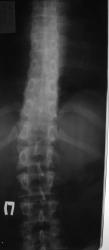

Пол пациента: Женский пол Тип патологии: Другое Область исследования: Скелетно-мышечная система Методы исследования: Rg Женщина, 29 лет, жалобы на боли в спине. Правомерно ли говорить о spinae bifidae Th 11? https://radiomed.ru/sites/default/files/styles/case_slider_image/public/user/2211/dsc00981.jpg?itok=_qg76Ozt ID:9985 Thu, 09/12/2010 - 20:55 #1 Almo Offline Last seen: 18 hours 43 min ago Joined: 28.09.2008 - 18:50 Posts: 8284 Правомочно. Mon, 13/12/2010 - 19:59 #2 Zimyshka Offline Last seen: 8 years 9 months ago Joined: 13.11.2009 - 18:26 Posts: 53 Спасибо за комментарий. Просто удивило такое место расположения, и выглядет она как у детей до 6 лет, где можно ее считать физиологической. Mon, 13/12/2010 - 21:49 #3 Almo Offline Last seen: 18 hours 43 min ago Joined: 28.09.2008 - 18:50 Posts: 8284 Да, вы правы, spina bifida такой локализации редко встречается.

Да, вы правы, spina bifida такой локализации редко встречается.